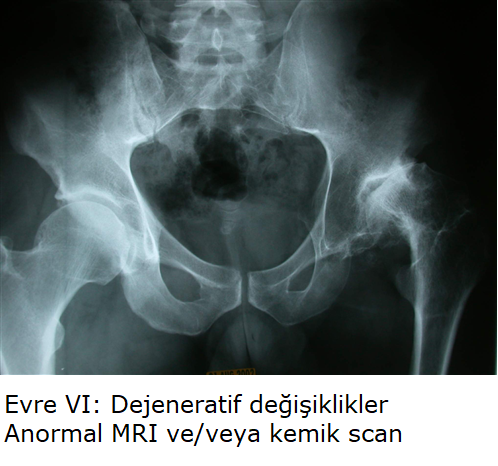

Evre IV: Eklem aralığında daralma, ileri osteoartrit. Terminal safha.

C. Kırmızı Bölge (Post-Collapse / Mekanik İflas - Evre III/IV)

Profil: Crescent Sign (+), çökme gerçekleşmiş. Tutulum >%50.

Strateji (Rekonstrüktif): Genç hastalarda yükü kaydırmak için Osteotomi; ileri evrede Total Kalça Artroplastisi (THA - Kalça Protezi). Cerrahi sonrası diğer kalçayı korumak için profilaktik protokol başlatılır.